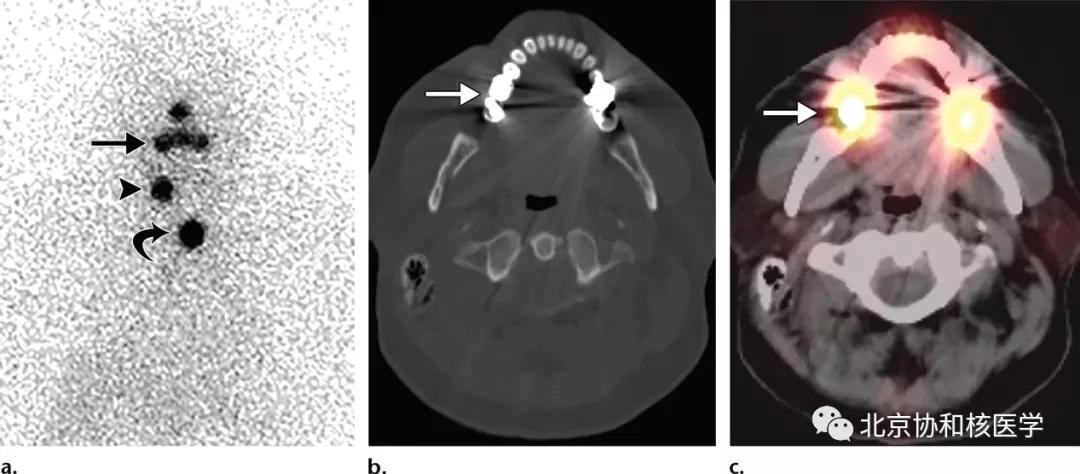

60岁男性,甲状腺全切除术后(乳头状癌),碘扫见颈部残余甲状腺及颈部淋巴结转移,此外上牙修复处见碘摄取,考虑可能为带负电的碘离子与带正电的金属材料结合并在局部滞留所致:

鼻腔脓肿所致碘摄取,其下方可见颈部残余甲状腺:

鼻腔息肉所致碘摄取,同时可见颈部残余甲状腺组织: